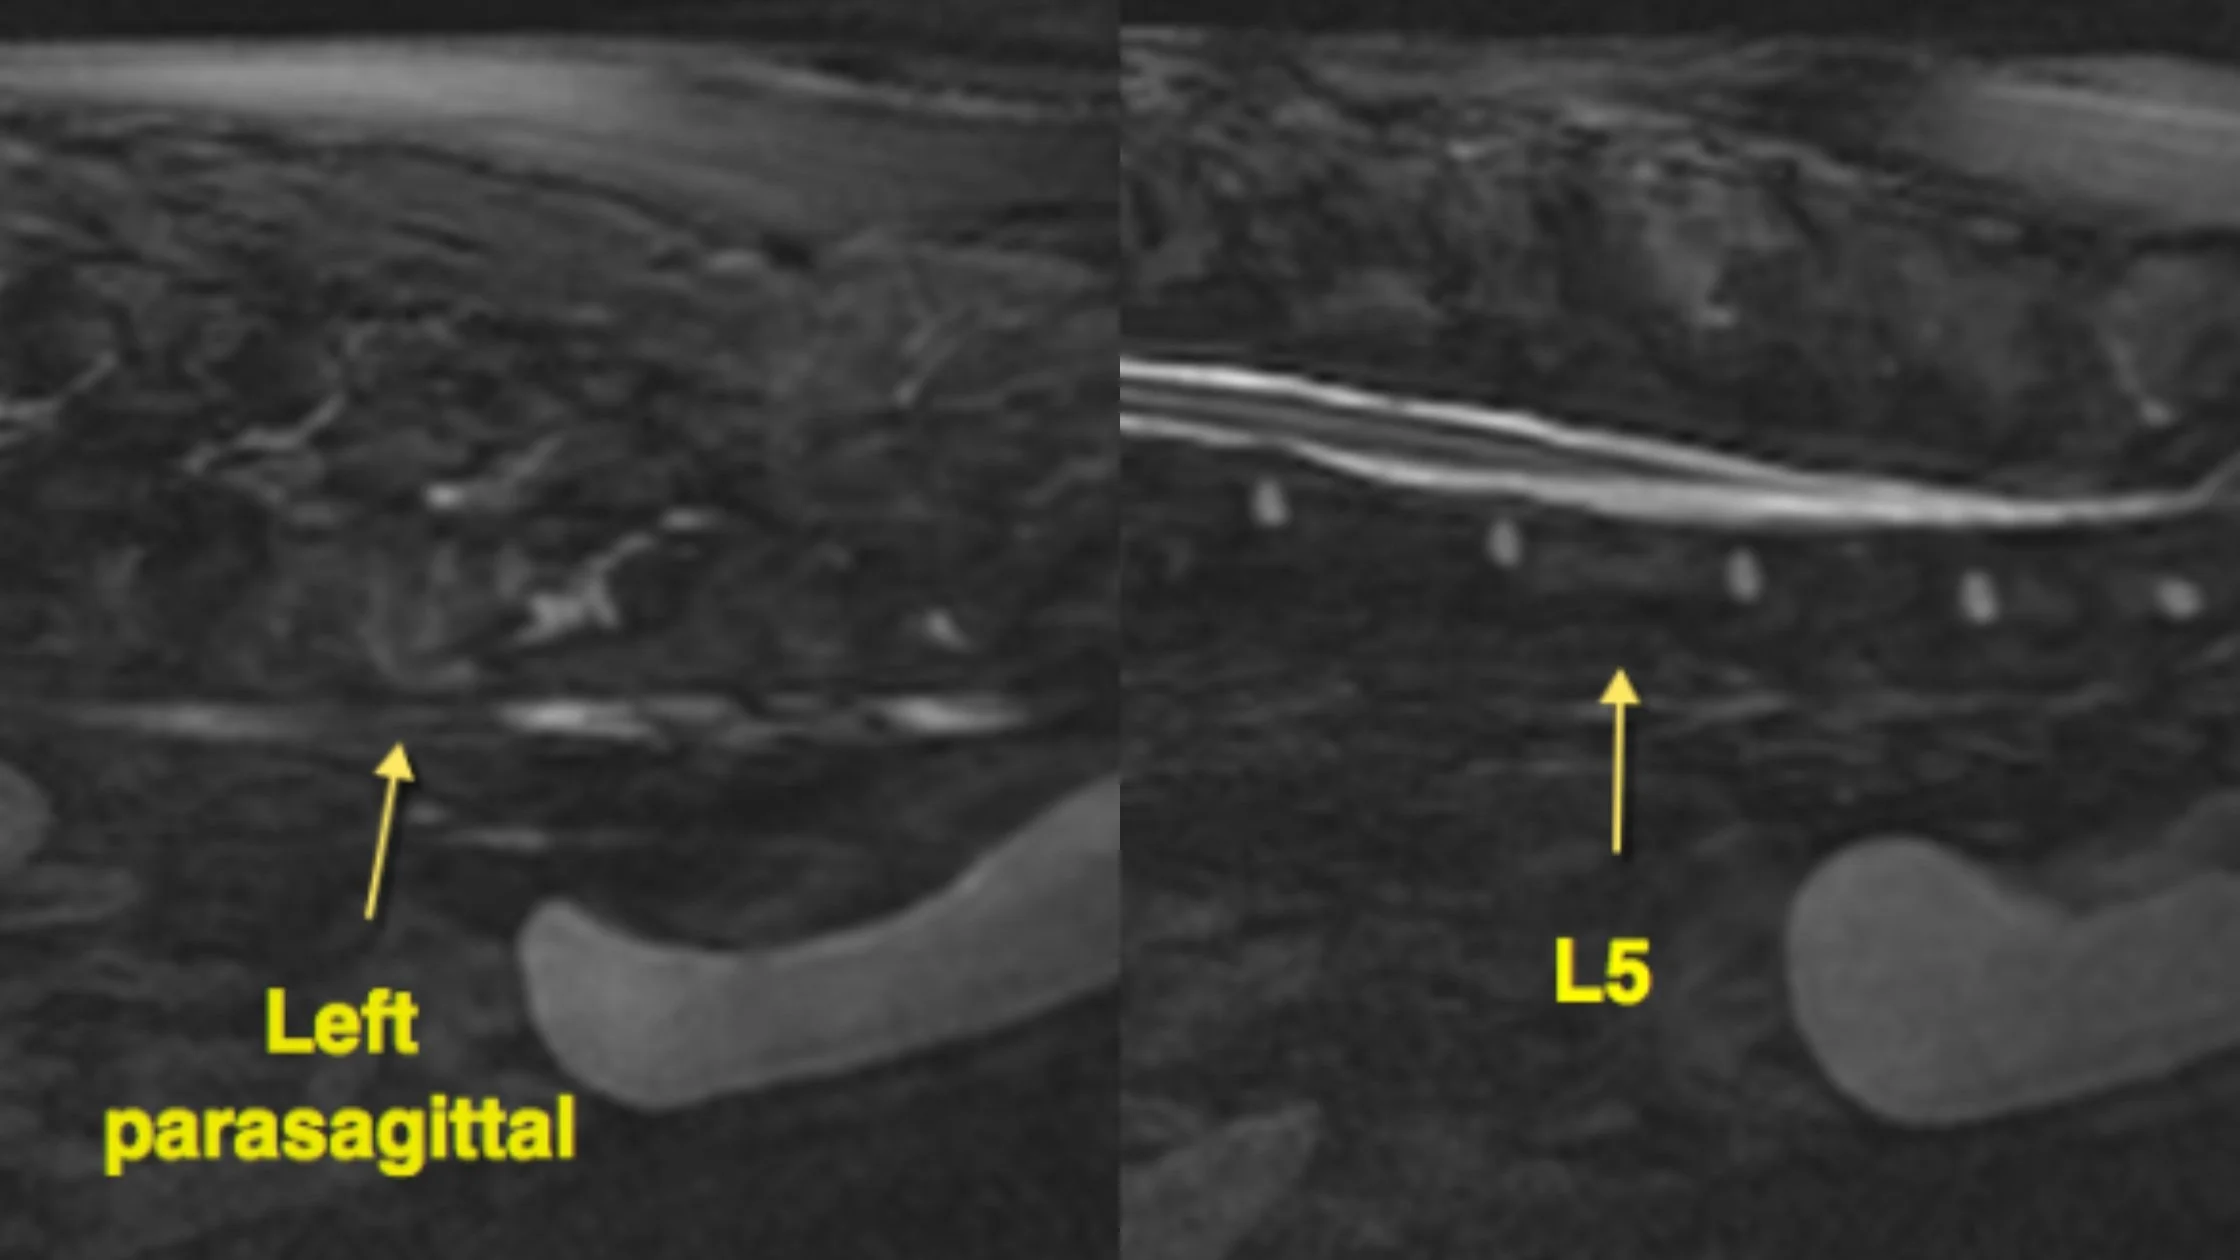

Split STIR MRI images showing sagittal and parasagittal views of a left iliopsoas muscle tear in a dog.

STIR MRI reveals focal hyperintensity in the left iliopsoas muscle consistent with acute strain injury.

• Hyperintensity within the left iliopsoas muscle at the level of L5, consistent with acute inflammation and tearing

• No compressive lesions in the spinal cord or nerve roots

• Normal disc spaces and vertebral alignment